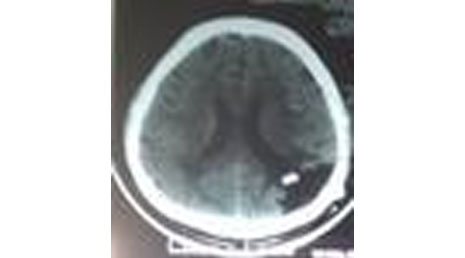

25. Cranial gunshot.